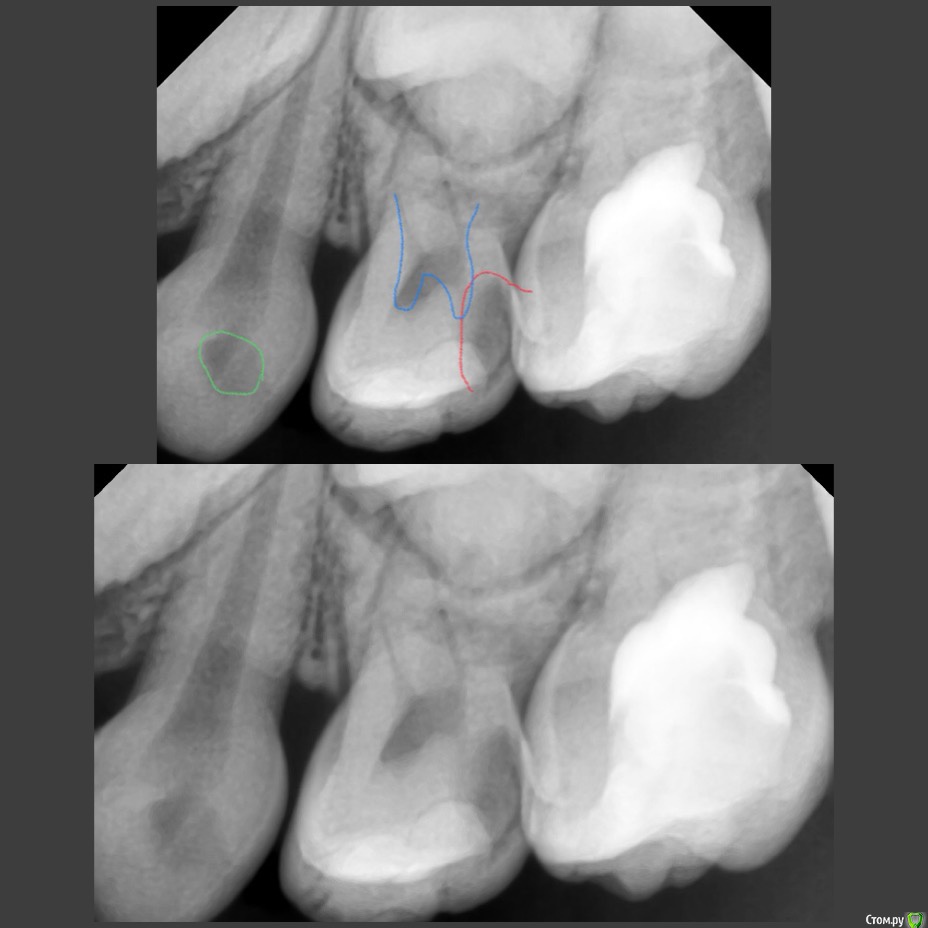

CRAZYDUCK Опубликовано 30 мая, 2018 Автор Поделиться Опубликовано 30 мая, 2018 Лечение 7.4 . Необратимый пульпит 7.4 зуба . В данном случае хорошо видно , что после ампутации гемостаз не наступает ( полость зуба заполнена кровью). Позже выложу случай со спонтанным гемостазом . Одного критерия , который бы со 100% вероятностью помогал понять , что нужна экстирпация нет . ❗Жалобы —если была самопроизвольная боль , которая не была связана с приемом пищи или выраженное последействие после пищи, боль купировалась приемом обезболивающего . Болит так , что ребёнок плачет . Самопроизвольная боль есть - скорее всего экстирпация ( если не удаление зуба).❗RVG если полость пульпы сообщается с кариозной полостью , то скорее всего экстирпация - учитывать проекцию тоже нужно .❗Гемостаз должен наступить через 4-5 минут после ампутации, если его нет - экстирпация .В данном случае боль была только кратковременная после приёма жесткой пищи . Преп, экстирпация ( Sxмашинный протейпер ), потом до 25.02 ручными , гипохлорит 3%, Йодотин в каналы , IRM культя , коронка фиксирована на Айрекс Цем . Обратите внимание - во время обработки зуба под Коронку - все в хлам и платок и десна . Предупреждаем родителей о дискомфорте , связанном с травмированием десны. 7 Ссылка на комментарий

CRAZYDUCK Опубликовано 30 мая, 2018 Автор Поделиться Опубликовано 30 мая, 2018 Про обратимый пульпит .( ампутацию) Лечение методом витальной АМПУТАЦИИ. Даше в июле 6 лет . Познакомились мы полтора года назад , но сотрудничать не получилось , направлены для лечения в условиях общего обезболивания ( наркоз ) к ☺ @toothfairymila После лечения в условиях наркоза дети легче идут на контакт . Ребёнка не узнать - если до лечения в наркозе Даша даже в кресло садилась со слезами , то после - милые подарки , осторожно , но готова сотрудничать . Даша внимательно смотрит на моих ассистентов , взгляд изучающий ( можно этому человеку доверять или нет ). Маме Даши огромное спасибо - очень ответственно относится к регулярным осмотрам . Выявили скрытые кариозные полости и Даша доверилась лечиться в обычных условиях ( без наркоза ). 6.4 - обратимый пульпит , изначально было обширное разрушение , восстановлено пломбой в наркозе , поэтому лепить там пломбу ещё больше нет смысла. После ампутации -спонтанный гемостаз ( сравните с предыдущим случаем). Промываем ХГ 2% , мта на устья , IRM , коронка. 6.5 - обширная реставрация окклюзионно и начался кариес на медиальной контактной поверхности . Зуб должен меняться примерно в 10 лет ( 9-11 лет средний срок), то есть хочется , чтобы он постоял ещё года четыре , поэтому покрываем коронкой . Ждём Дашу на осмотр через 3-4 месяца.П.С. На заметку молодым коллегам - На снимке обвела зелёным нерентгенконтрастную реставрацию на зубе 6.3 , похоже на кариес , но это очень хорошая реставрация ! 1 Ссылка на комментарий